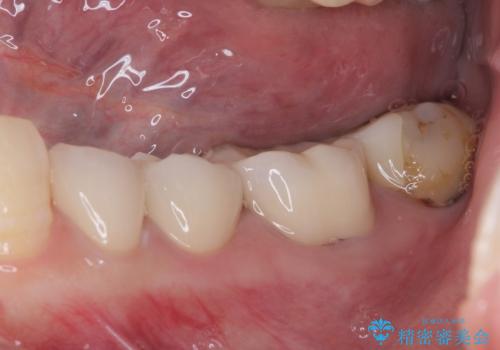

痛みが引いた後、不揃いな見た目で気になっていた左下の奥歯とともにオールセラミッククラウンにて補綴治療を行うこととしました。

右上の歯は、第二小臼歯の初回処置後に痛みを感じなくなったため、他の歯については問題なしと診断しました。

将来ホワイトニングをされるとのことで、前歯よりもやや白い色合いのオールセラミッククラウンを選択されました。